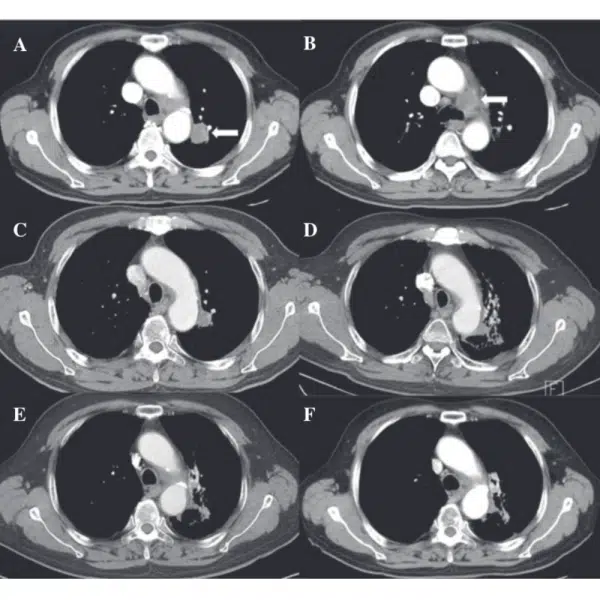

A 75-year-old male an active smoker with a 50-pack-year history. Simple chest radiography showed a mass-like lesion in the left upper lobe. Computed tomography (CT) revealed a 2.6-cm irregular mass with peripheral enhancement in the left upper lobe abutting the descending thoracic aorta. The left lower paratracheal lymph node was enlarged and appeared to have extra nodal extension and recurrent laryngeal nerve invasion.

Planned treatments of RT combined with oncothermia were completed without interruption. Acute toxicity was limited to mild odynophagia, which subsided with conservative management. No skin reaction developed. Follow-up CT showed a complete tumor response along with signs of radiation pneumonitis and fibrosis around the treated region; however, the patient developed no specific associated symptoms. There was an improvement in the presenting symptom of hoarseness and the patient was alive without any evidence of the disease at 18 months after treatment.